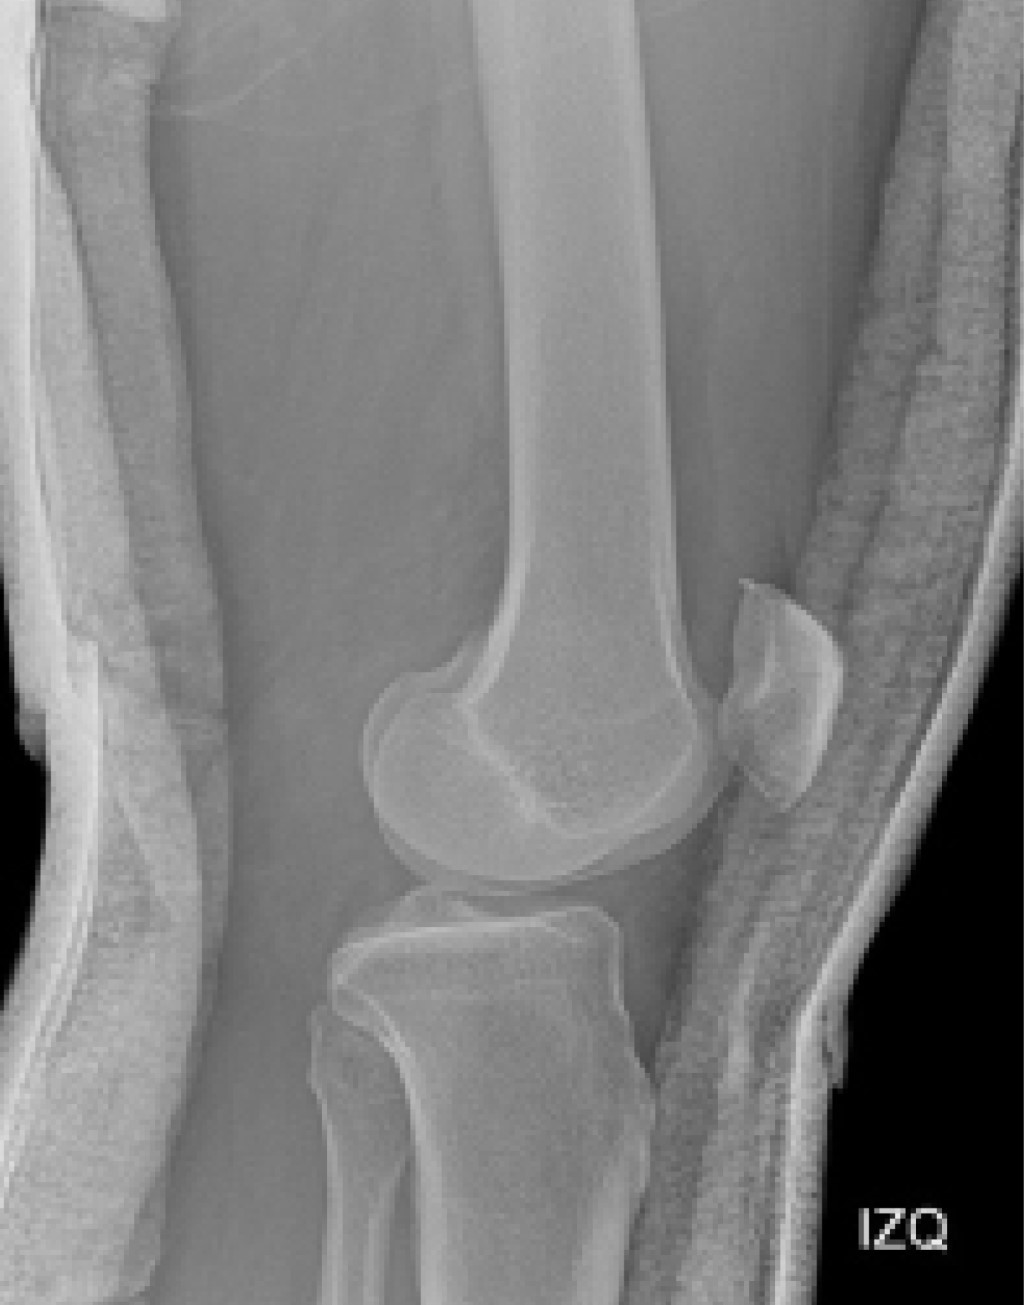

El segundo escenario es mucho más complejo de abordar, se presenta cuando el paciente ingresa al servicio de urgencias con la rodilla reducida, haciendo del diagnóstico de la luxación de rodilla un reto para el clínico, en el cual las radiografías iniciales tienen un papel valioso en la evidencia de hallazgos característicos que pueden sugerir el diagnóstico de luxación como la apertura de los espacios articulares tibiofemorales (Figura 4), fracturas del cóndilo femoral, fracturas de espinas tibiales anterior y posterior, signo del ligamento arcuato (Figura 5) o el signo de Segond (Figura 6).3

El "signo del arcuato" corresponde a una avulsión en la cabeza del peroné, sitio donde se inserta el complejo arcuato (ligamento arcuato, ligamento poplíteo fibular, tendón conjunto del bíceps y ligamento colateral fibular), sugestivo de lesión de la esquina posterolateral de la rodilla; hay que tener en cuenta que hasta 89% de pacientes con lesiones de esquina posterolateral presentan lesión de ligamento cruzado anterior o posterior y que debe considerarse en contexto de sospecha de luxación de rodilla.42,43

La fractura o signo de Segond es una fractura avulsiva en la región proximolateral de la tibia secundaria a traumas rotacionales de la rodilla por tensión del ligamento anterolateral. Recientemente se ha asociado esta fractura con las rupturas del ligamento cruzado anterior y con el impacto que tiene en los resultados de la reconstrucción del mismo.

Figura 5

Figura 6